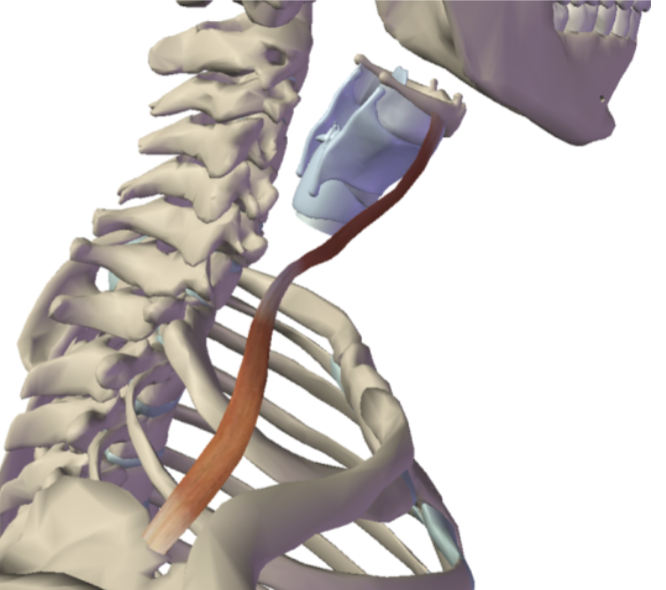

What is this muscle?

Omohyoid (depress hyoid)